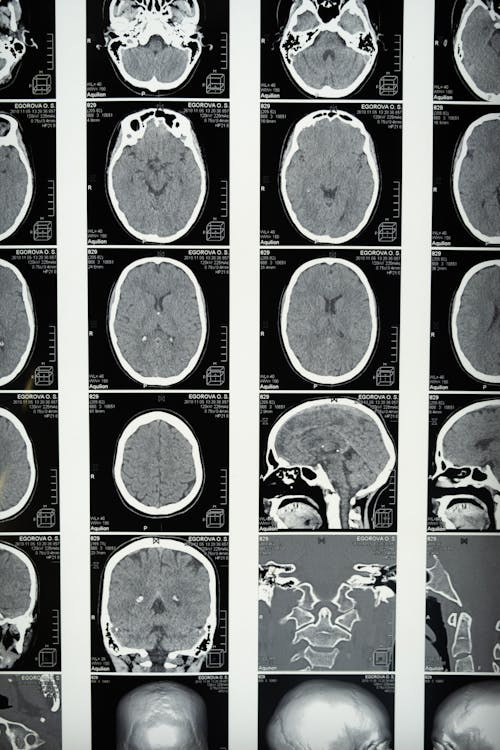

뇌졸중 진단 방법

1️⃣ CT(컴퓨터단층촬영)

→ 출혈 여부를 빠르게 확인 (응급 시 필수)

2️⃣ MRI(자기 공명영상)

→ 뇌경색 초기 병변까지 정밀하게 확인 가능